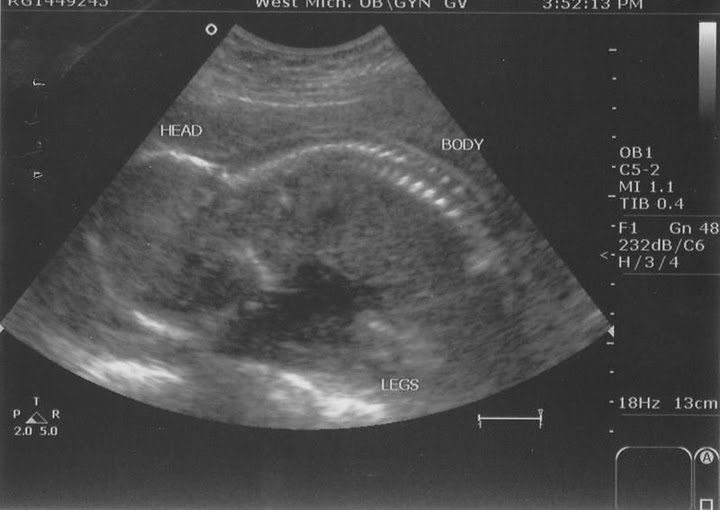

Some pictures from the ultrasound:

We almost didn't get to see what she was. She was sitting cross-legged and was very comfortable that way.